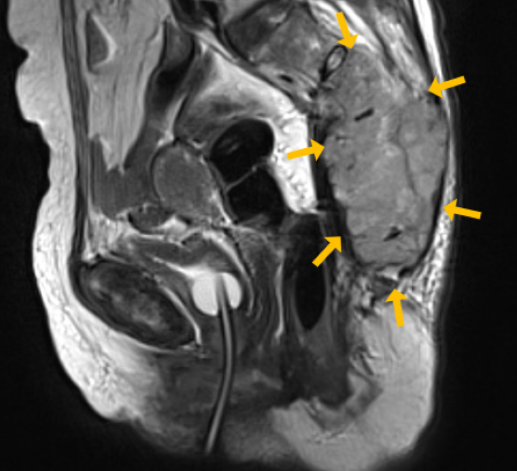

MRI상 꼬리뼈부위의 전이암

영상 검사: X-ray, CT, MRI 등을 통해 골절, 탈구, 감염, 종양 여부 등을 평가

x-ray 및 MRI상 골절등을 확인.